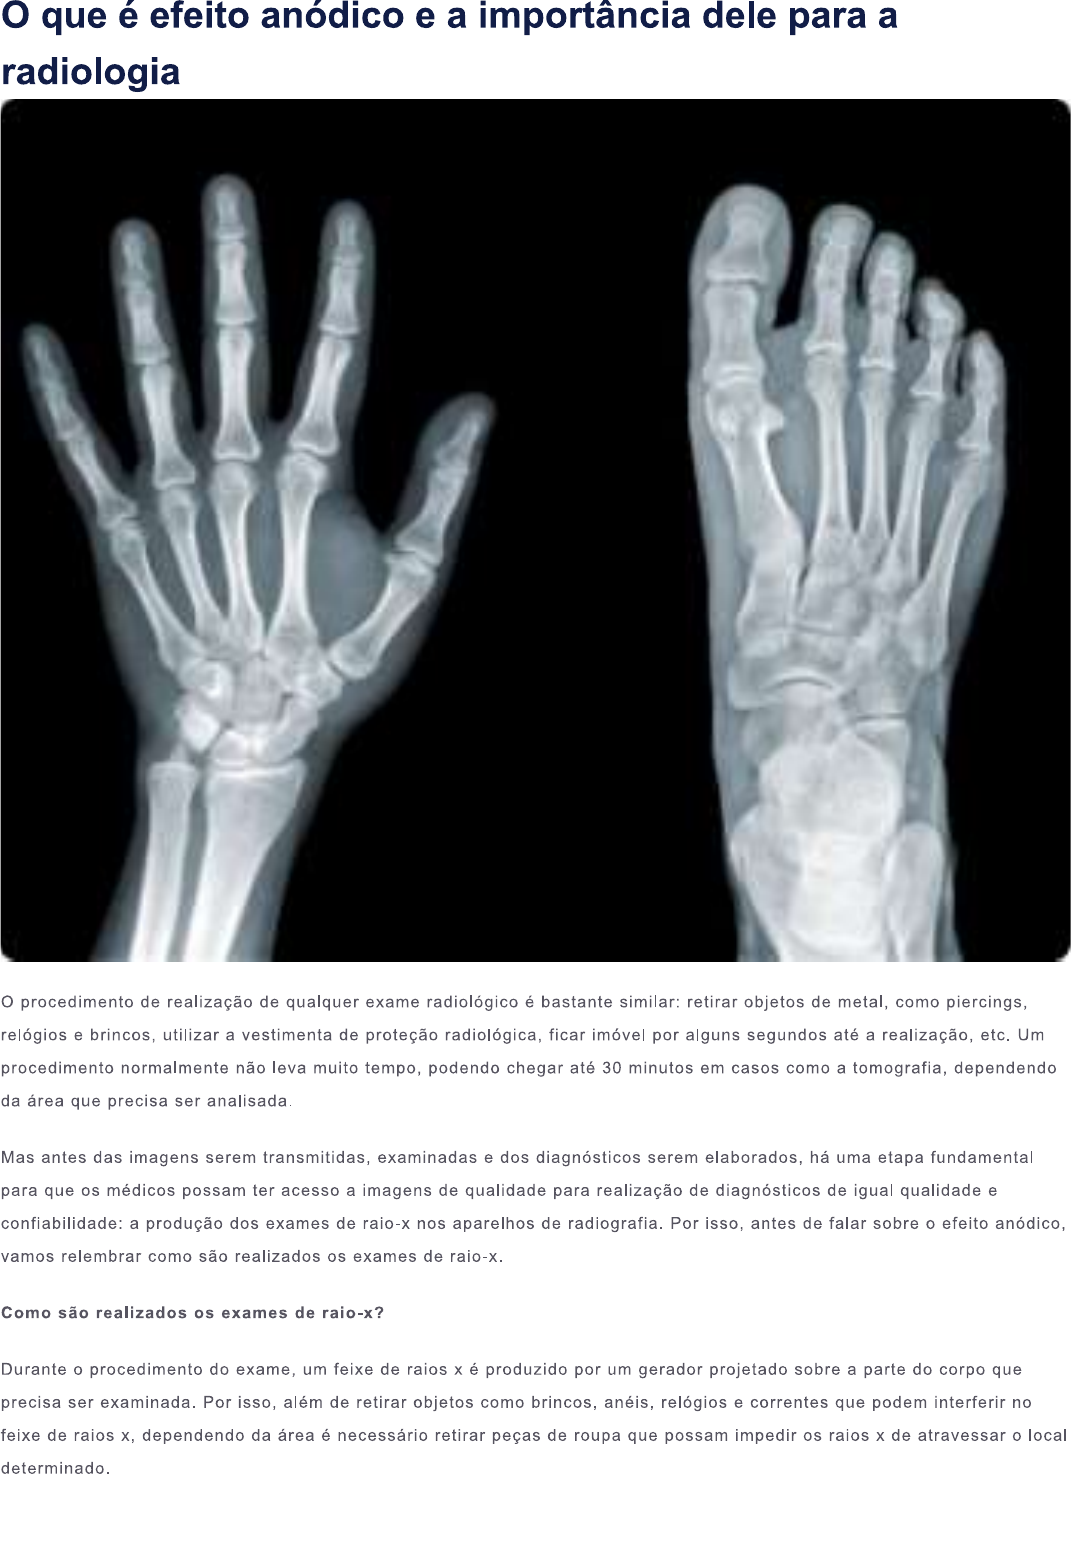

Prévia do material em texto